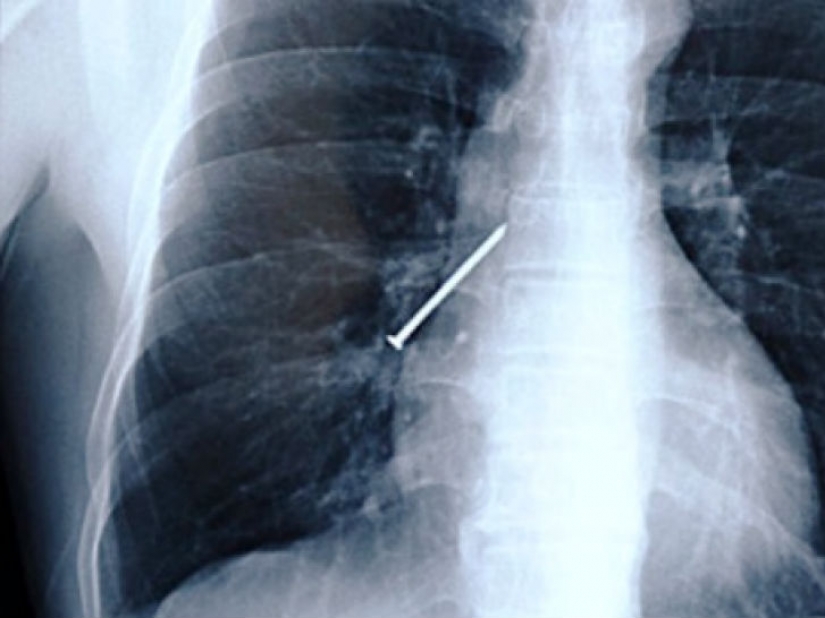

Have you ever held in his teeth a nail when your hands are busy with a hammer? Here's the men from China, which during operation coughed.